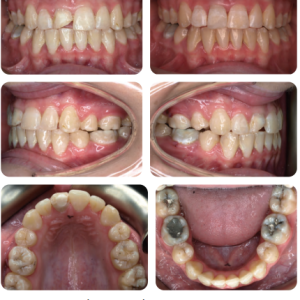

Bệnh nhân nữ 15 tuổi có sai khớp cắn hạng I trên nền xương hạng I với kích thước dọc trung bình, phức tạp bởi chen chúc nặng, R13 và R33 mọc lệch, còn nhiều răng sữa và R11 bị chấn thương (Hình 1).

- Sức khỏe răng miệng kém (các miếng trám trên những răng hàm lớn thứ nhất hàm dưới, chấn thương R11, hủy khoáng sớm ở cổ răng của những răng hàm lớn thứ nhất hàm dưới)

- Chen chúc nặng ở cả 2 cung răng

- R13 lệch (lệch trong, về phía khẩu cái) và R33 (theo đường cung răng).

- R22 cắn chéo

- Còn nhiều răng sữa